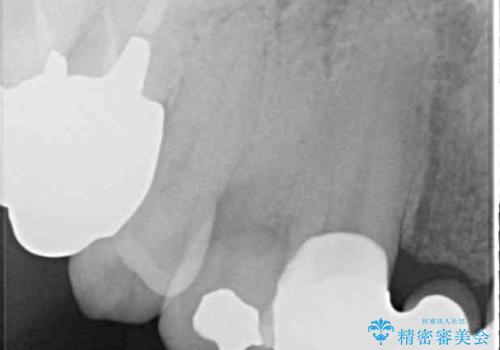

露出していた歯根や金属の縁が見えてしまい、なかなか口を開けて笑うことができなかったのですが、歯肉の位置に縁を合わせることで自然な仕上がりとなりました。

ブリッジの隙間にものが詰まったり、空気が抜けたりすることも無くなり、話しやすさも改善することができました。

露出していた歯根が覆われるため、歯冠が長く見えてしまうことが懸念されましたが特に気になることはなく、患者様には大変満足していただきました。